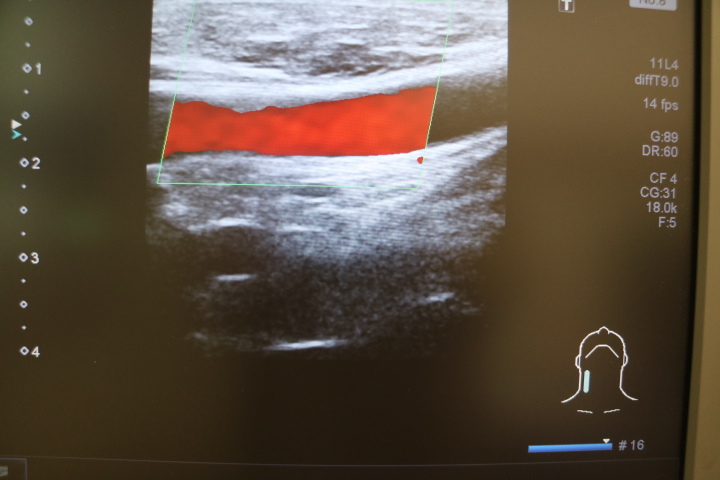

・頸部動脈超音波検査(頸動脈の詰まり具合・動脈硬化検査)

・甲状腺・上下肢血管エコー(動脈・静脈血行障害の検査)